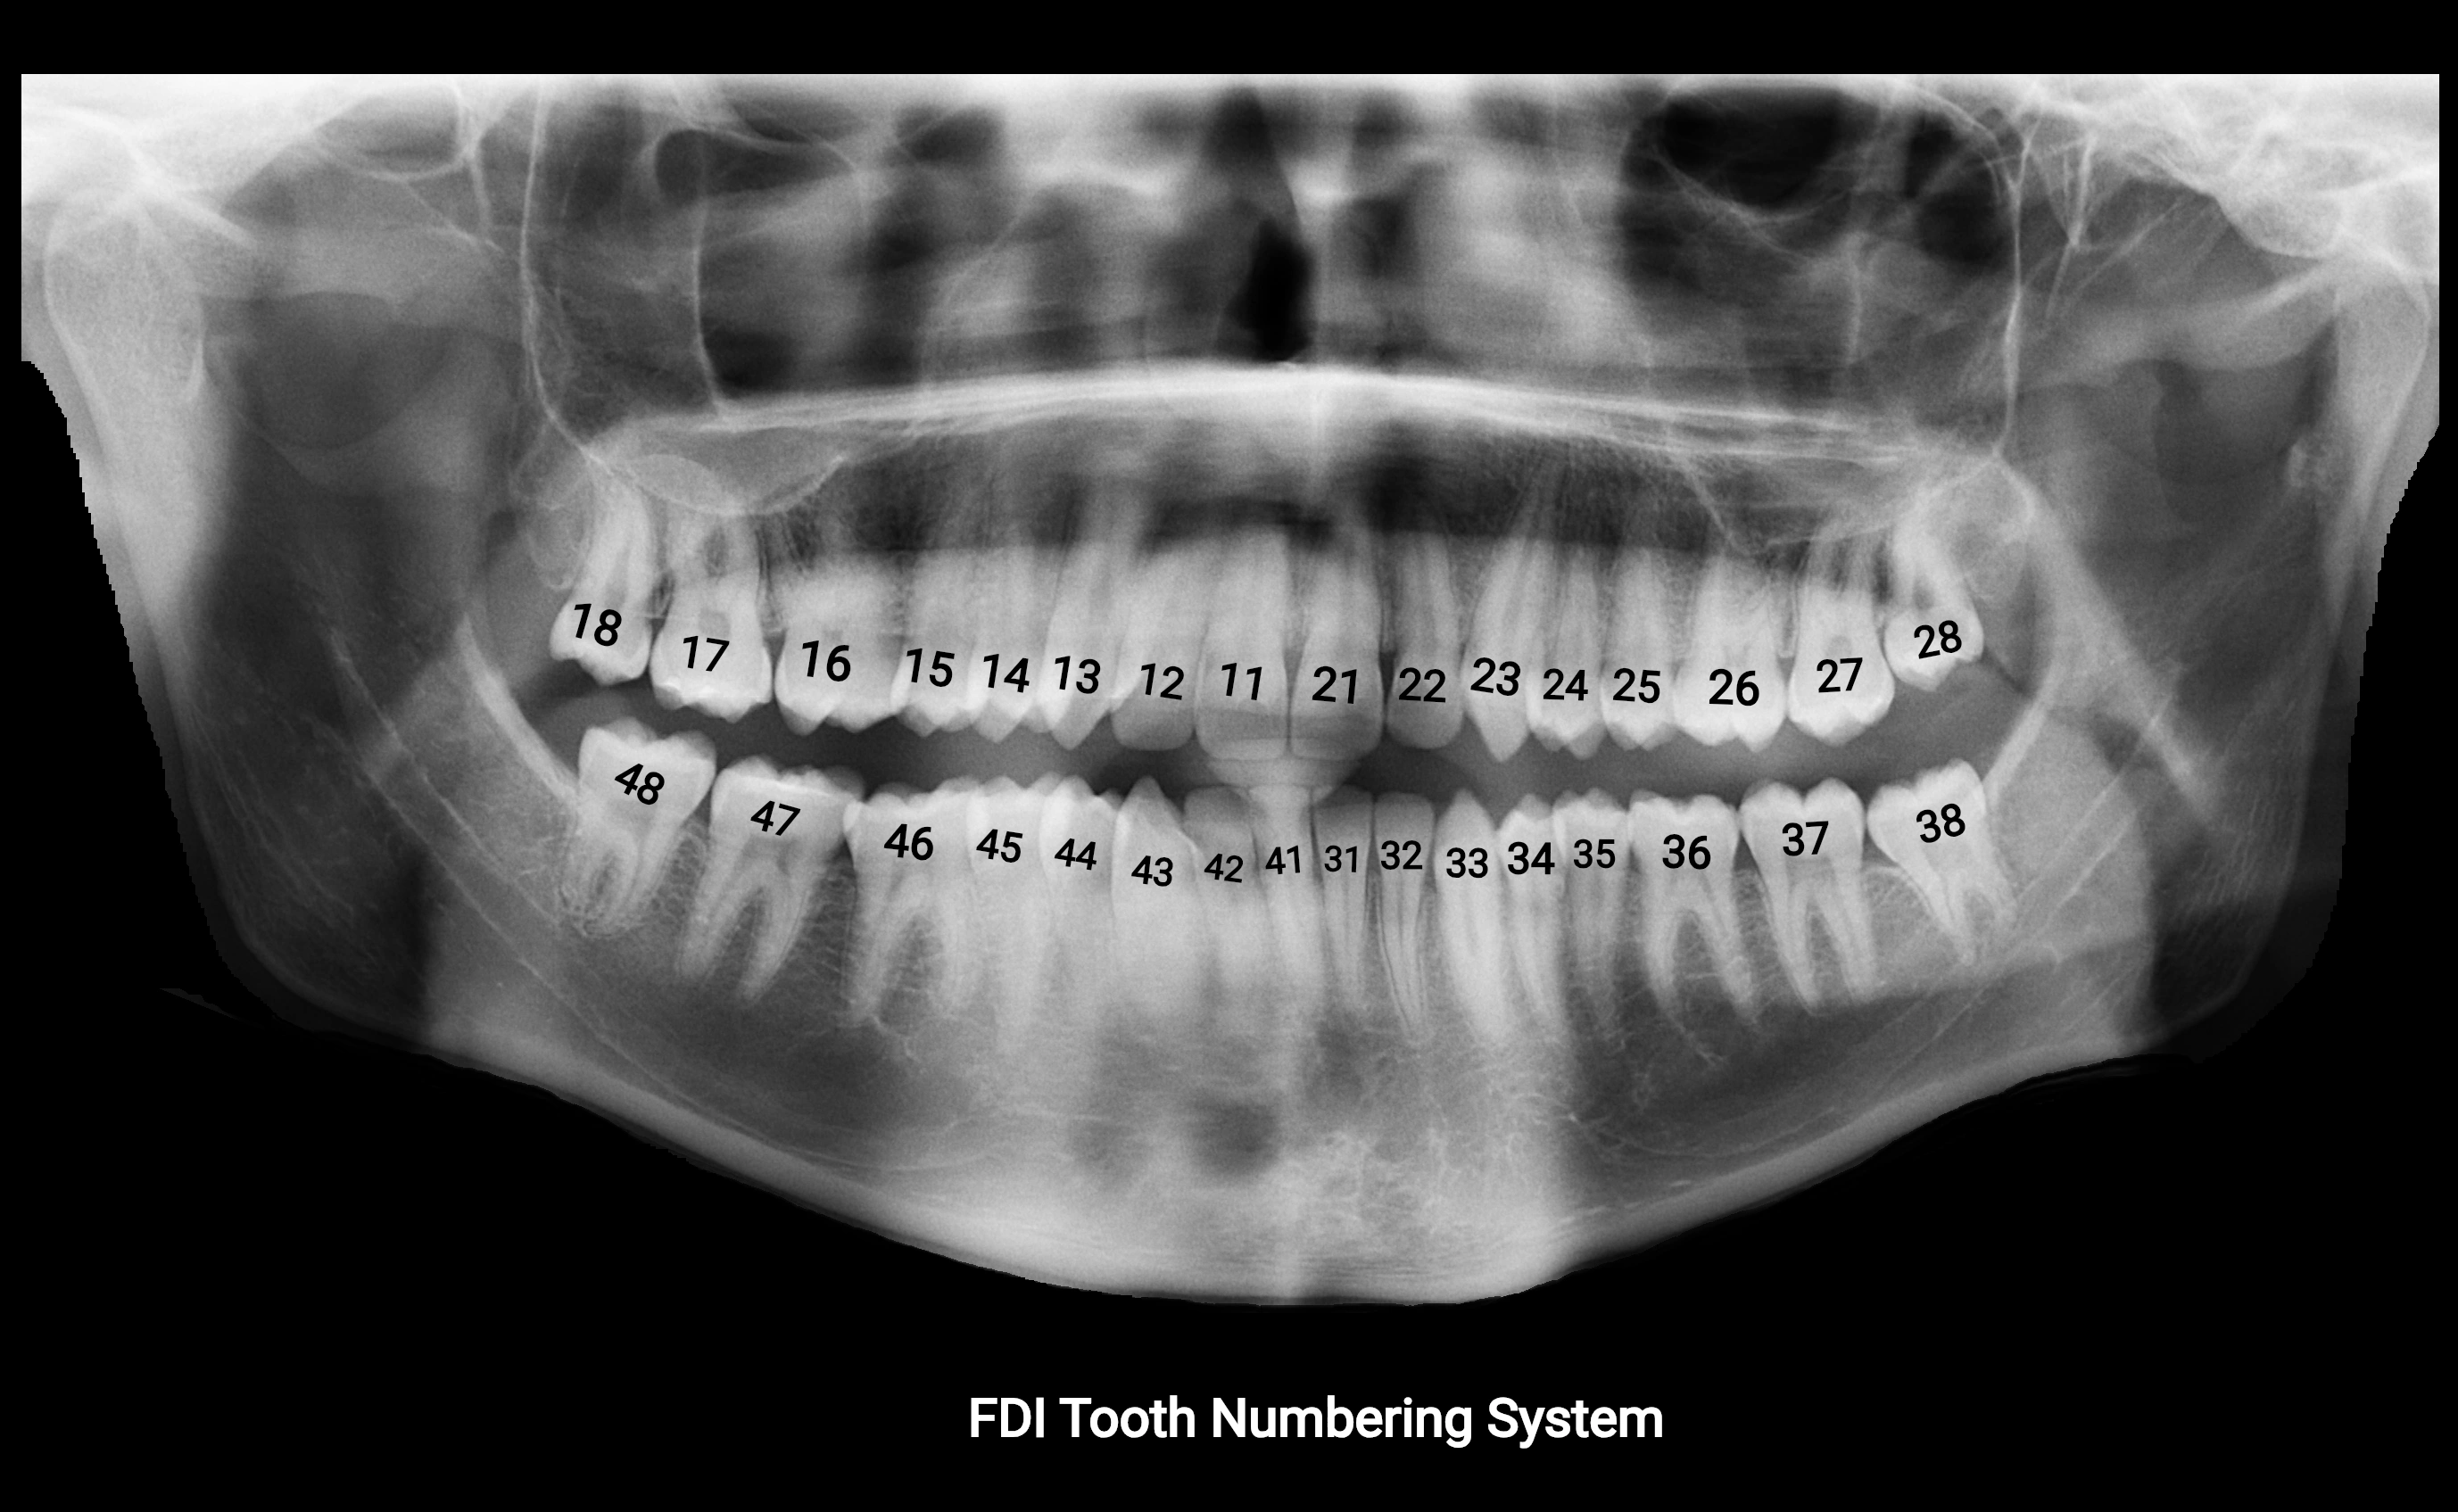

Alveolar process of maxilla

The alveolar process of the maxilla is the bony ridge of the maxilla that houses the upper teeth, extending from the anterior nasal spine to the maxillary tuberosity posteriorly. It consists of compact cortical bone on its outer surfaces and trabecular (cancellous) bone internally, with alveolar sockets (dental alveoli) forming individualized cavities for each tooth. The alveolar process develops in association with tooth eruption and resorption, adapting its shape and volume throughout life. It also forms part of the hard palate medially and contributes to the architecture of the midface, supporting the upper lip, cheeks, and nasal floor.